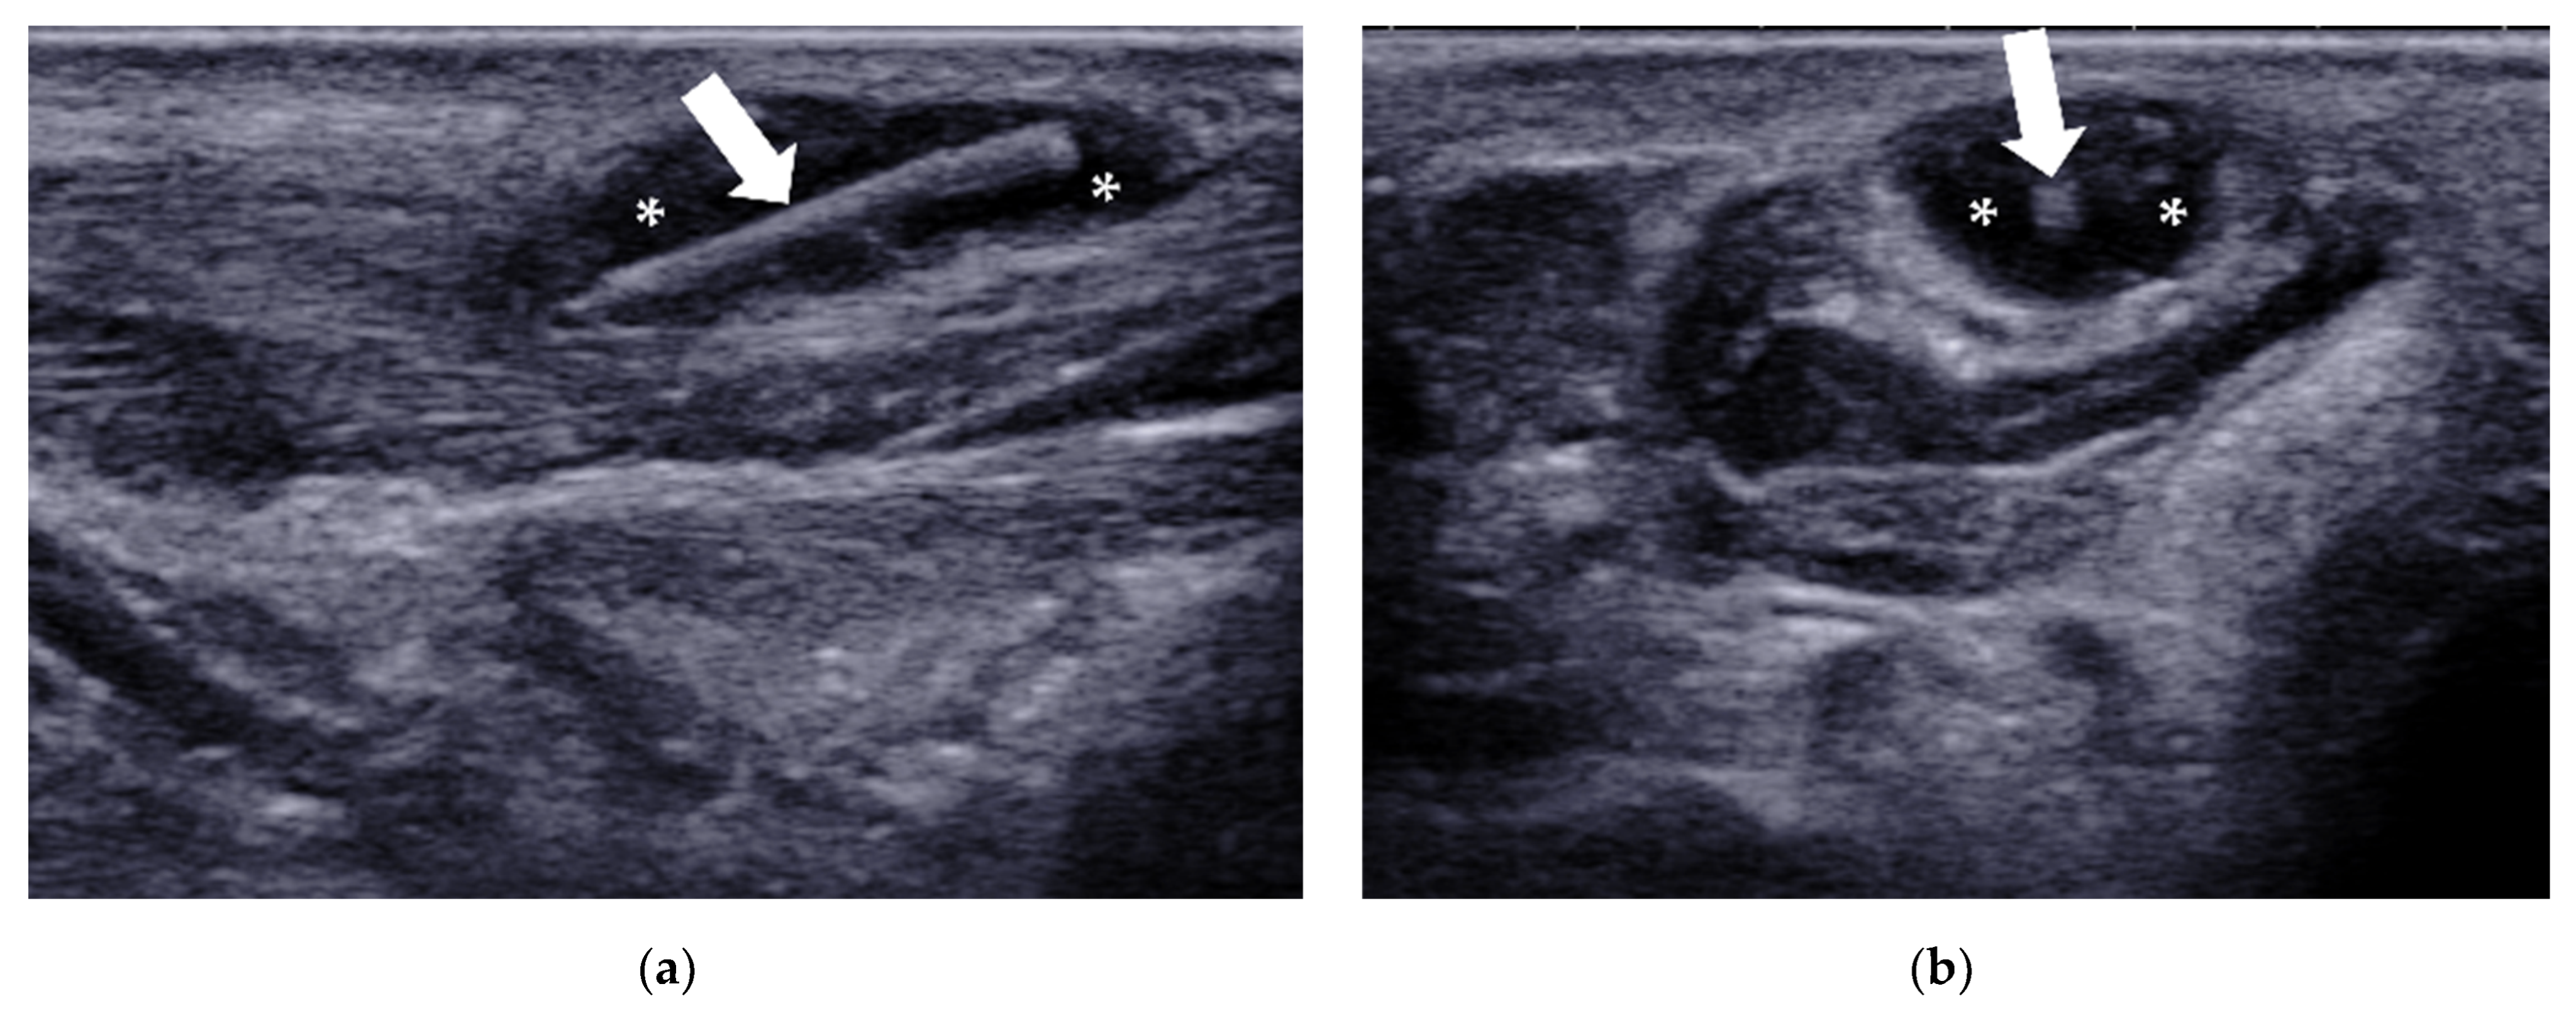

| Tenosynovitis | / | tendon sheath distension with surrounding effusion, “target” sign in transverse view |

4.2.3. Intermetatarsal Bursitis

| Intermetatarsal bursitis | intermetatarsal spaces between 2nd and 3rd toes | hypoechoic mass with increased vascularity, compressible |